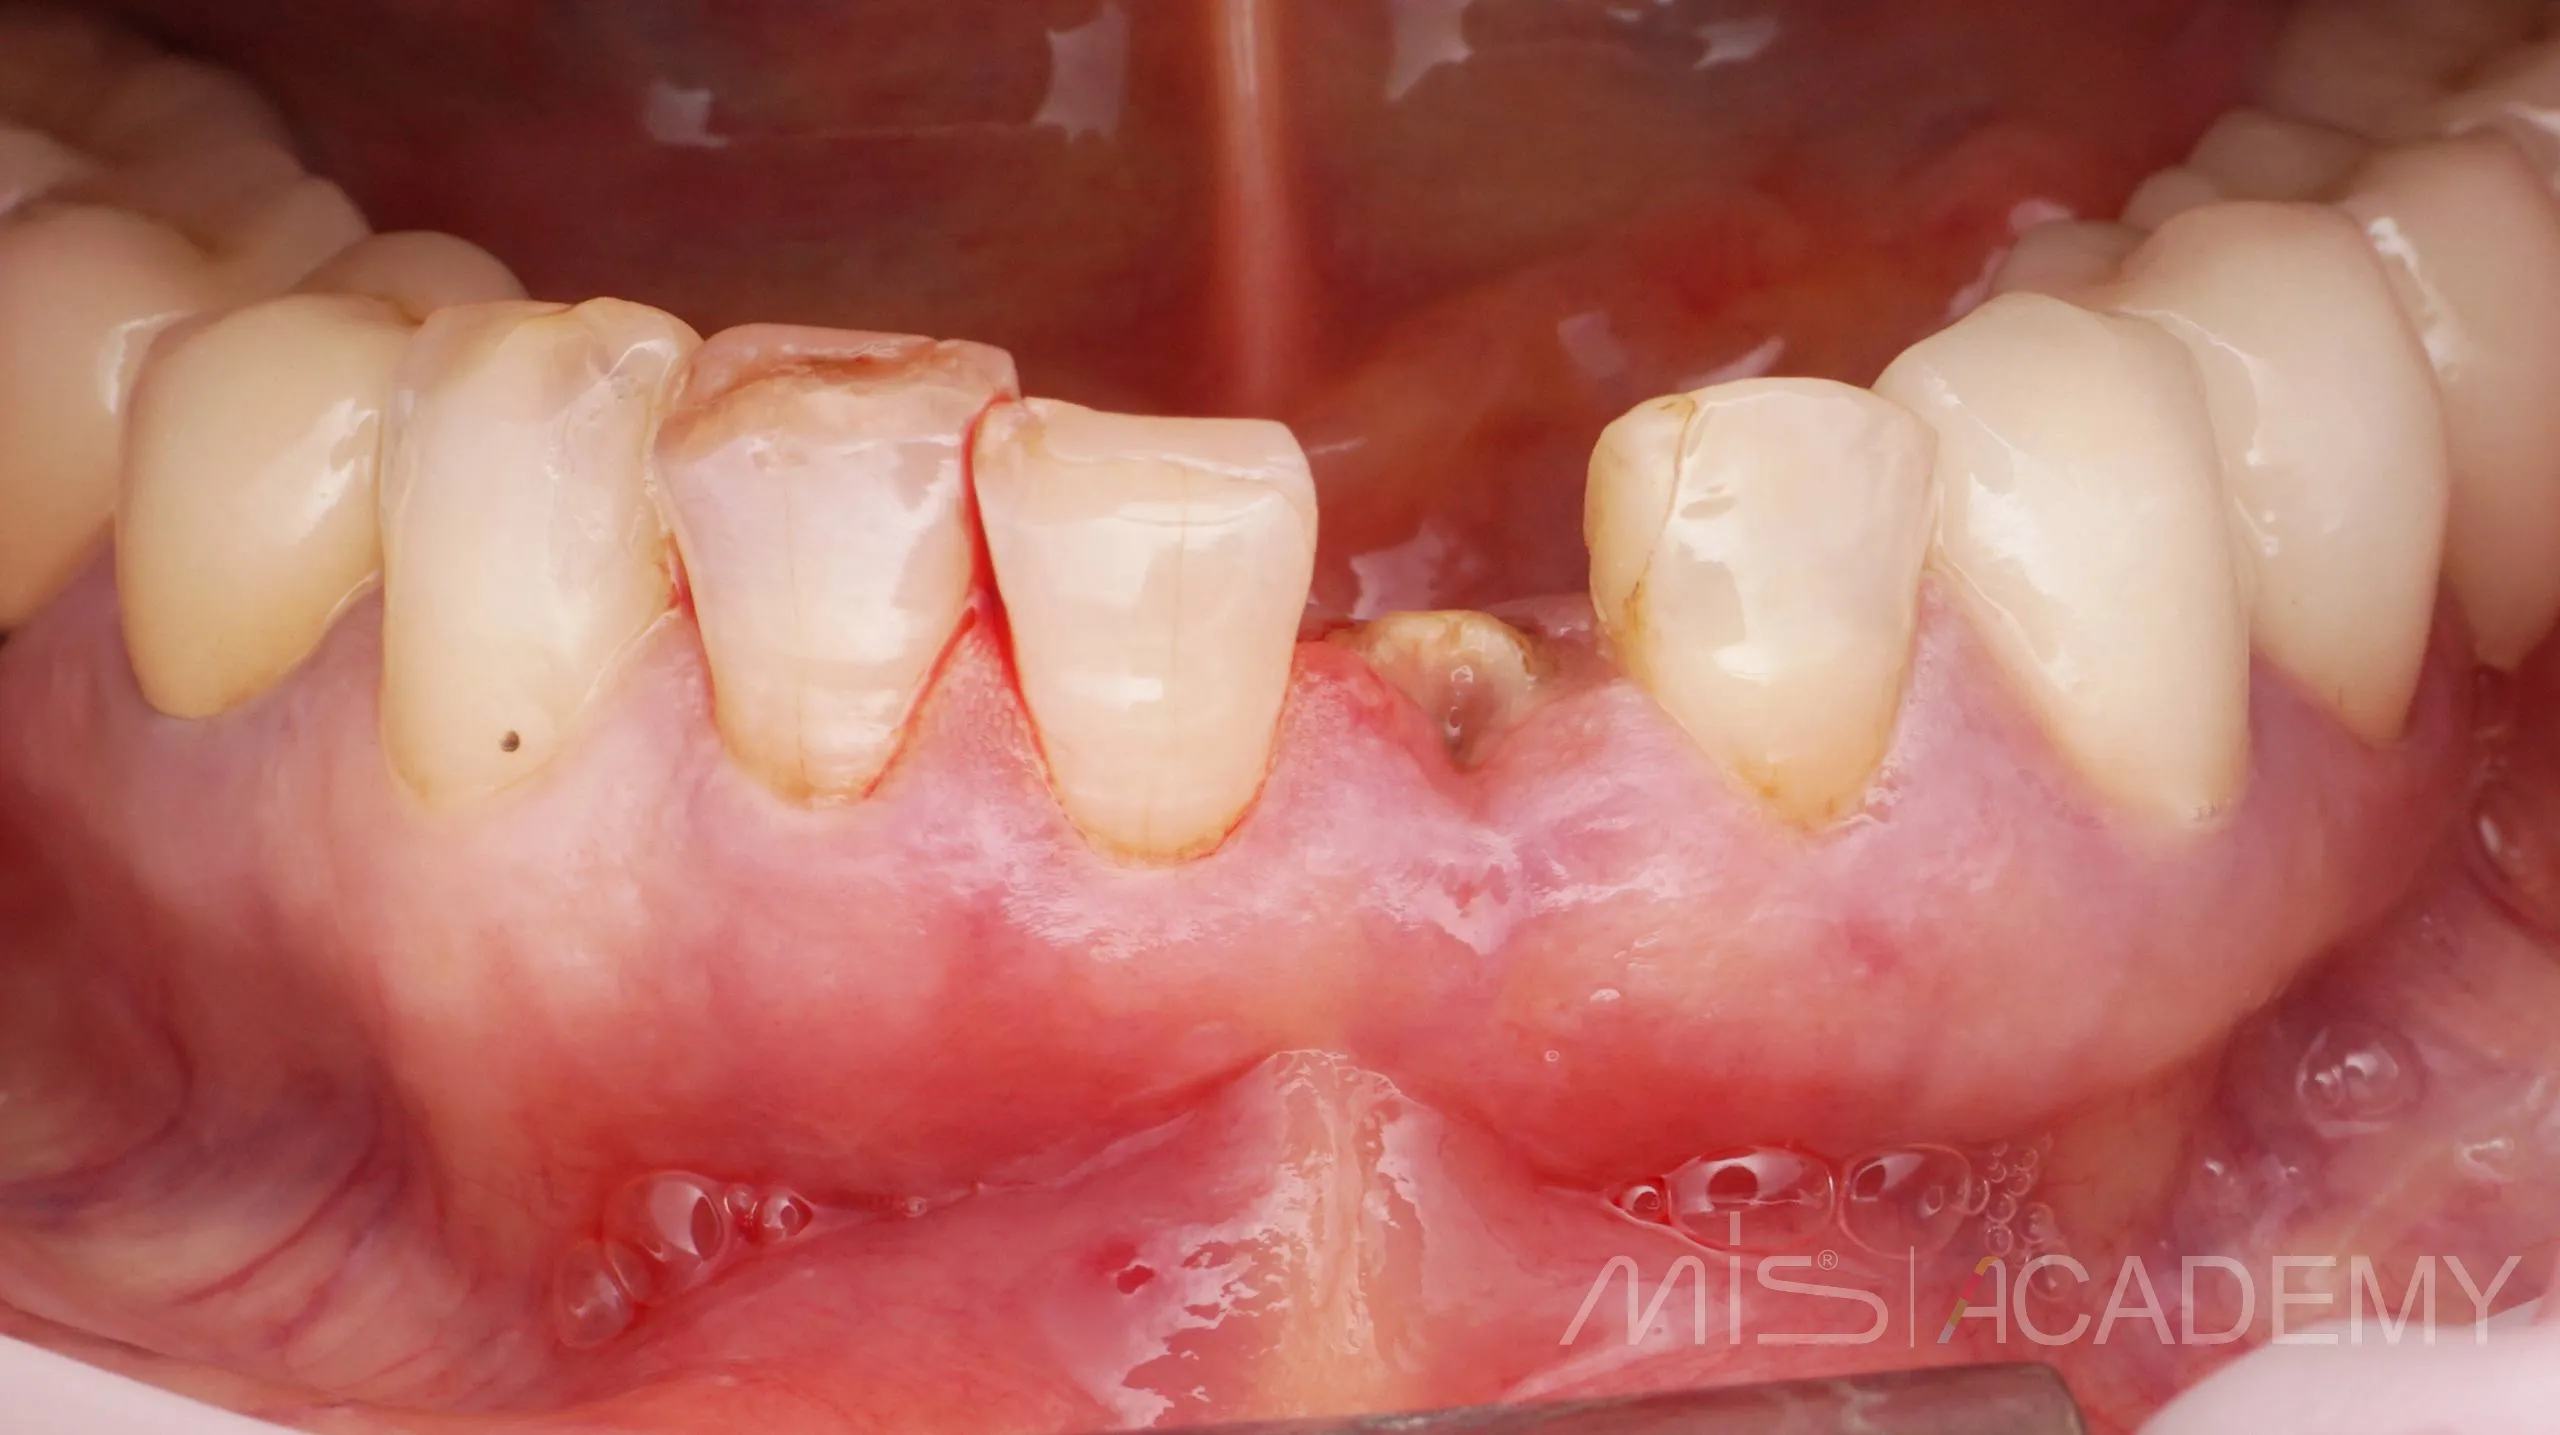

Одномоментная имплантация MIS С1

— Индивидуальный Zr формирователь десны на Connect абатменте